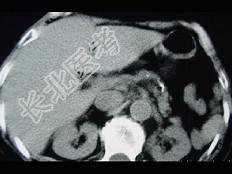

- 单项选择题女,54岁, 中上腹痛,体重减轻, 消化不良,脂肪痢、便量多、泡沫状。影像检查如下图, 最佳诊断是 ( )

B、慢性胰腺炎